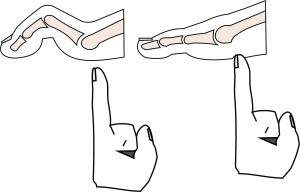

Das Nervenleiden beginnt meist mit einer Verminderung der Empfindung, welche von den Patienten meist nicht bemerkt wird. Daneben kommt es zu einer Beeinträchtigung der Muskelfunktion, woraus Fehlstellungen wie Krallen- bzw. Hammerzehen und Hallux valgus entstehen. Dadurch wird an typischen Stellen ein hoher Knochendruck auf die darüber liegende Haut hervorgerufen, der – anders als beim Nervengesunden – keine Beschwerden auslöst. An den Druckstellen können Wunden entstehen, die – obwohl schmerzlos – dennoch gefährlich sind, weil sie schwere Infektionen ermöglicht, die bisweilen mit einer Amputation behandelt werden müssen.

Ziel einer Operation ist es, Knochendruck, der zu einer Wunde geführt hat, zu beseitigen. Für unkomplizierte Situationen und zur Prophylaxe von Fußulzerationen kommen die Operationstechniken in Betracht, die auch zur Korrektur am Vorfuß wie bei Hallux valgus oder Hammerzehen angewandt werden. Hier können Sehnen so durchtrennt werden, dass sich die Fehlstellungen ausgleichen (Minimalinvasive Therapie von Krallenzehen). Wenn die Fehlstellungen fortgeschritten sind, ist es wie bei schweren Entzündungen erforderlich, Teile von Knochen zu entfernen z. B. die Köpfchen der Zehengrundglieder oder der Mittelfußknochen. Es gibt mittlerweile minimalinvasive Methoden, bei denen durch die Haut mit speziellen Fräsen Knochendruck entfernt werden können.